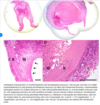

Aneurysm wall histology

66

Amyloid angiopathy:develops when fibrillary proteins form a β-pleated sheet conformation that deposits in the walls of arterioles as amyloid, causing wall thickening and lumen narrowing; amyloid deposits can extend into the surrounding perivascular tissue, resem- bling senile plaques of Alzheimer disease (1) Histology: similar to lipohyalinosis except that amyloid angiopa- thy is congophilic (i.e., exhibits apple-green birefringence after Congo red staining) whereas lipohyalinosis is eosinophilic (i.e., stains with hematoxylin) (2) ICH from amyloid angiopathy often extends into an SAH because of the cortical location of the ICH (3) Genetics: most cases are sporadic and involve the amyloid pre- cursor protein (APP) (i.e., the amyloid β-protein 1-42 [Aβ1-42]) that is found in Alzheimer plaques (a) Rare hereditary forms of amyloid angiopathy (i) Icelandic-type amyloid angiopathy: mutations of cys- tatin C, a protease inhibitor that accumulates as amyloid when mutated; causes fatal ICH by 20–30 years of age (ii) Dutch-type amyloid angiopathy: mutations in APP that cause accumulation as amyloid; causes fatal ICH by 40 years of age (iii) Mutations of transthyretin, the thyroxine (T4) carrier protein